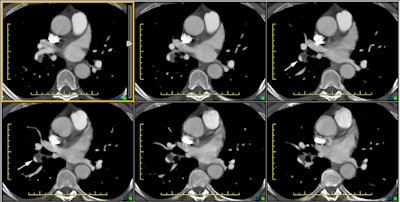

The CT scan below is from a patient with chronic pulmonary embolism. The white arrows denote vessels with thrombus that is eccentric and has been incorporated into the vessel walls.